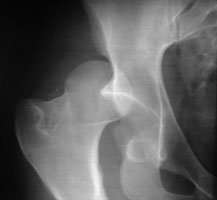

- Click on the image for a larger versionAAP radiograph of the right hip. There is posterior dislocation of the femoral head.

The majority of hip dislocations are posterior and due to impaction of the femoral head upon the acetabulum from direct force to the distal femur (generally against a dashboard). This usually results in fracture of the posterior rim of the acetabulum and may result in sciatic nerve injury. With anterior dislocation, the femoral head is displaced into the obturator or pubic region. With internal dislocation, the femoral head projects into the pelvic cavity.